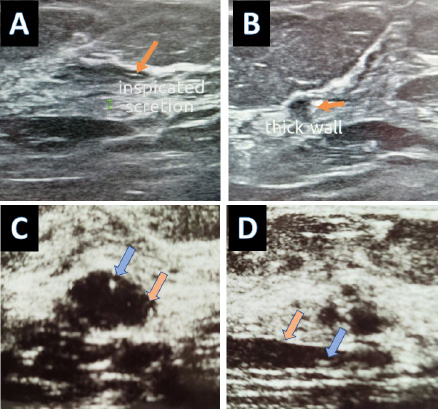

(A) Thin-walled ectatic duct with intraluminal inspissated secretion. (B) Thick wall ectatic duct with regional tubular duct ectasia suggesting mastitis (C) The ectatic duct resembles a cyst in a cross-section image (D) Longitudinal scan through duct ectasia showing internal echogenic debris; blue arrow.